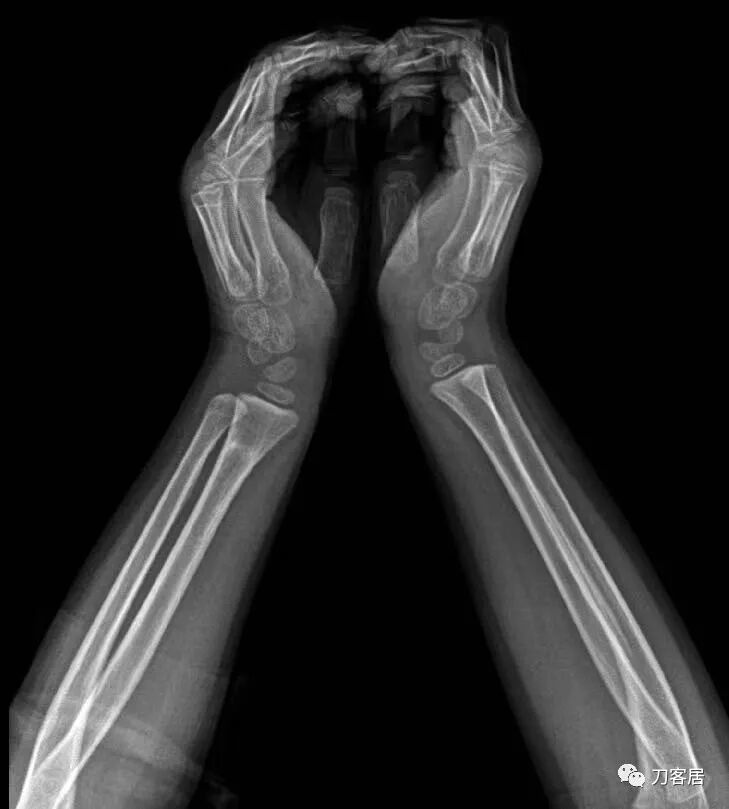

2021年7月21日,在中华骨科网儿童骨科病例讨论群里,看到了几张图片,是某仁慈医院的一位手外科医生做的手术,被某地器械厂家发在朋友圈里炫耀,有小儿骨科医生看不过去,就发群里请大家评论,引起众多小儿骨科医生的批评。

下面是这个6岁孩子,尺桡骨远端双骨折的术前及术后片子和外观照片。

1.  这是一个很简单的6岁儿童无移位的尺桡骨远端骨折。没有皮肤损伤,没有移位,没有骨折碎块儿。

2.  这个骨折处理起来也很简单,单纯的打石膏托或者中医的小夹板,或者正规的包括腕关节和肘关节的管型石膏外固定4周即可治愈该骨折。实在不行,如果这个孩子比较听话,不太调皮的话,用一本书,一个三角巾悬吊固定4周,都可以治愈该骨折。但是给这个患者用外固定架做了手术,而且桡骨远端的几颗克氏针距离骨折线太近,其中一枚克氏针进入到骨折间隙内。从这个术中图片来看,术者的外固定手术技术也有待于进一步的提高。毕竟术者应该还很年轻。从X线片来看,前臂及手的尺侧有不透光影,应该还使用了外固定石膏绷带托,而且我猜测应该是高分子的石膏绷带托,这个是纯属猜测,不一定是对的,不过如何解释前臂尺侧的不透光影呢?如果真是用了石膏绷带外固定的话,那为啥要做手术呢?外固定架术后就不该再用石膏绷带托辅助了。